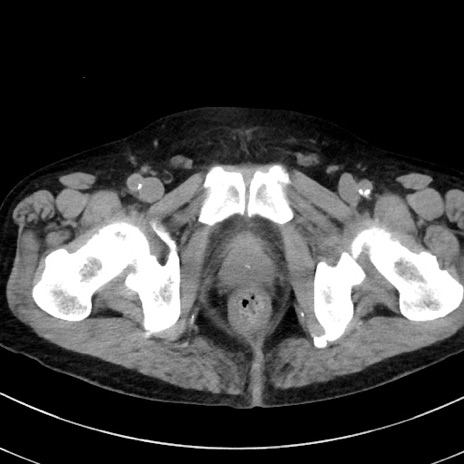

症例38(横断像)

【症例】70歳代 男性

【主訴】腹痛・嘔吐

【現病歴】昨晩より、嘔吐・腹痛あり。今朝になっても嘔吐あり。来院。

【既往歴】心臓バイパス手術、開腹胆摘、腸閉塞

【身体所見】BP 107/71mmHg、HR 116/min、腹部:平坦、軟、下腹部に軽度圧痛あり。反跳痛なし。

【データ】WBC 15100、CRP 0.32